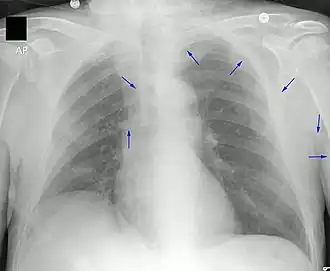

Ter controle wordt na afloop van het inbrengen een röntgenfoto (thorax) gemaakt om te zien of de lijn goed ligt. Als het inbrengen onverhoopt onvoldoende steriel is gebeurd (bijvoorbeeld doordat er te veel personen aan het bed waren bij het inbrengen), kan ontsteking van de ader in de arm (flebitis) met plaatselijke zwelling en roodheid optreden, die met uithalen van de PICC-lijn en tabletten antibioticum (bijvoorbeeld flucloxacilline) wordt bestreden. De afdeling Microbiologie van het ziekenhuis kan een afgeknipt stukje van de PICC-lijn onderzoeken op ziekteverwekkers. Eventueel wordt later opnieuw een PICC-lijn maar dan beter steriel ingebracht. Douchen met een PICC-lijn is trouwens enige tijd na het inbrengen mogelijk met een in plastic ingepakte arm. De behandelend verpleegkundige spoelt de lijn regelmatig door met bijvoorbeeld een zoutoplossing.

- ↑ (en) Note3.blogspot.com V. Dimov, M.D., Cleveland Clinic: Different Venous Catheters: What is PICC, Hickman, Quinton, and Port-A-Cath? Medisch commentaar bij deze röntgenfoto.